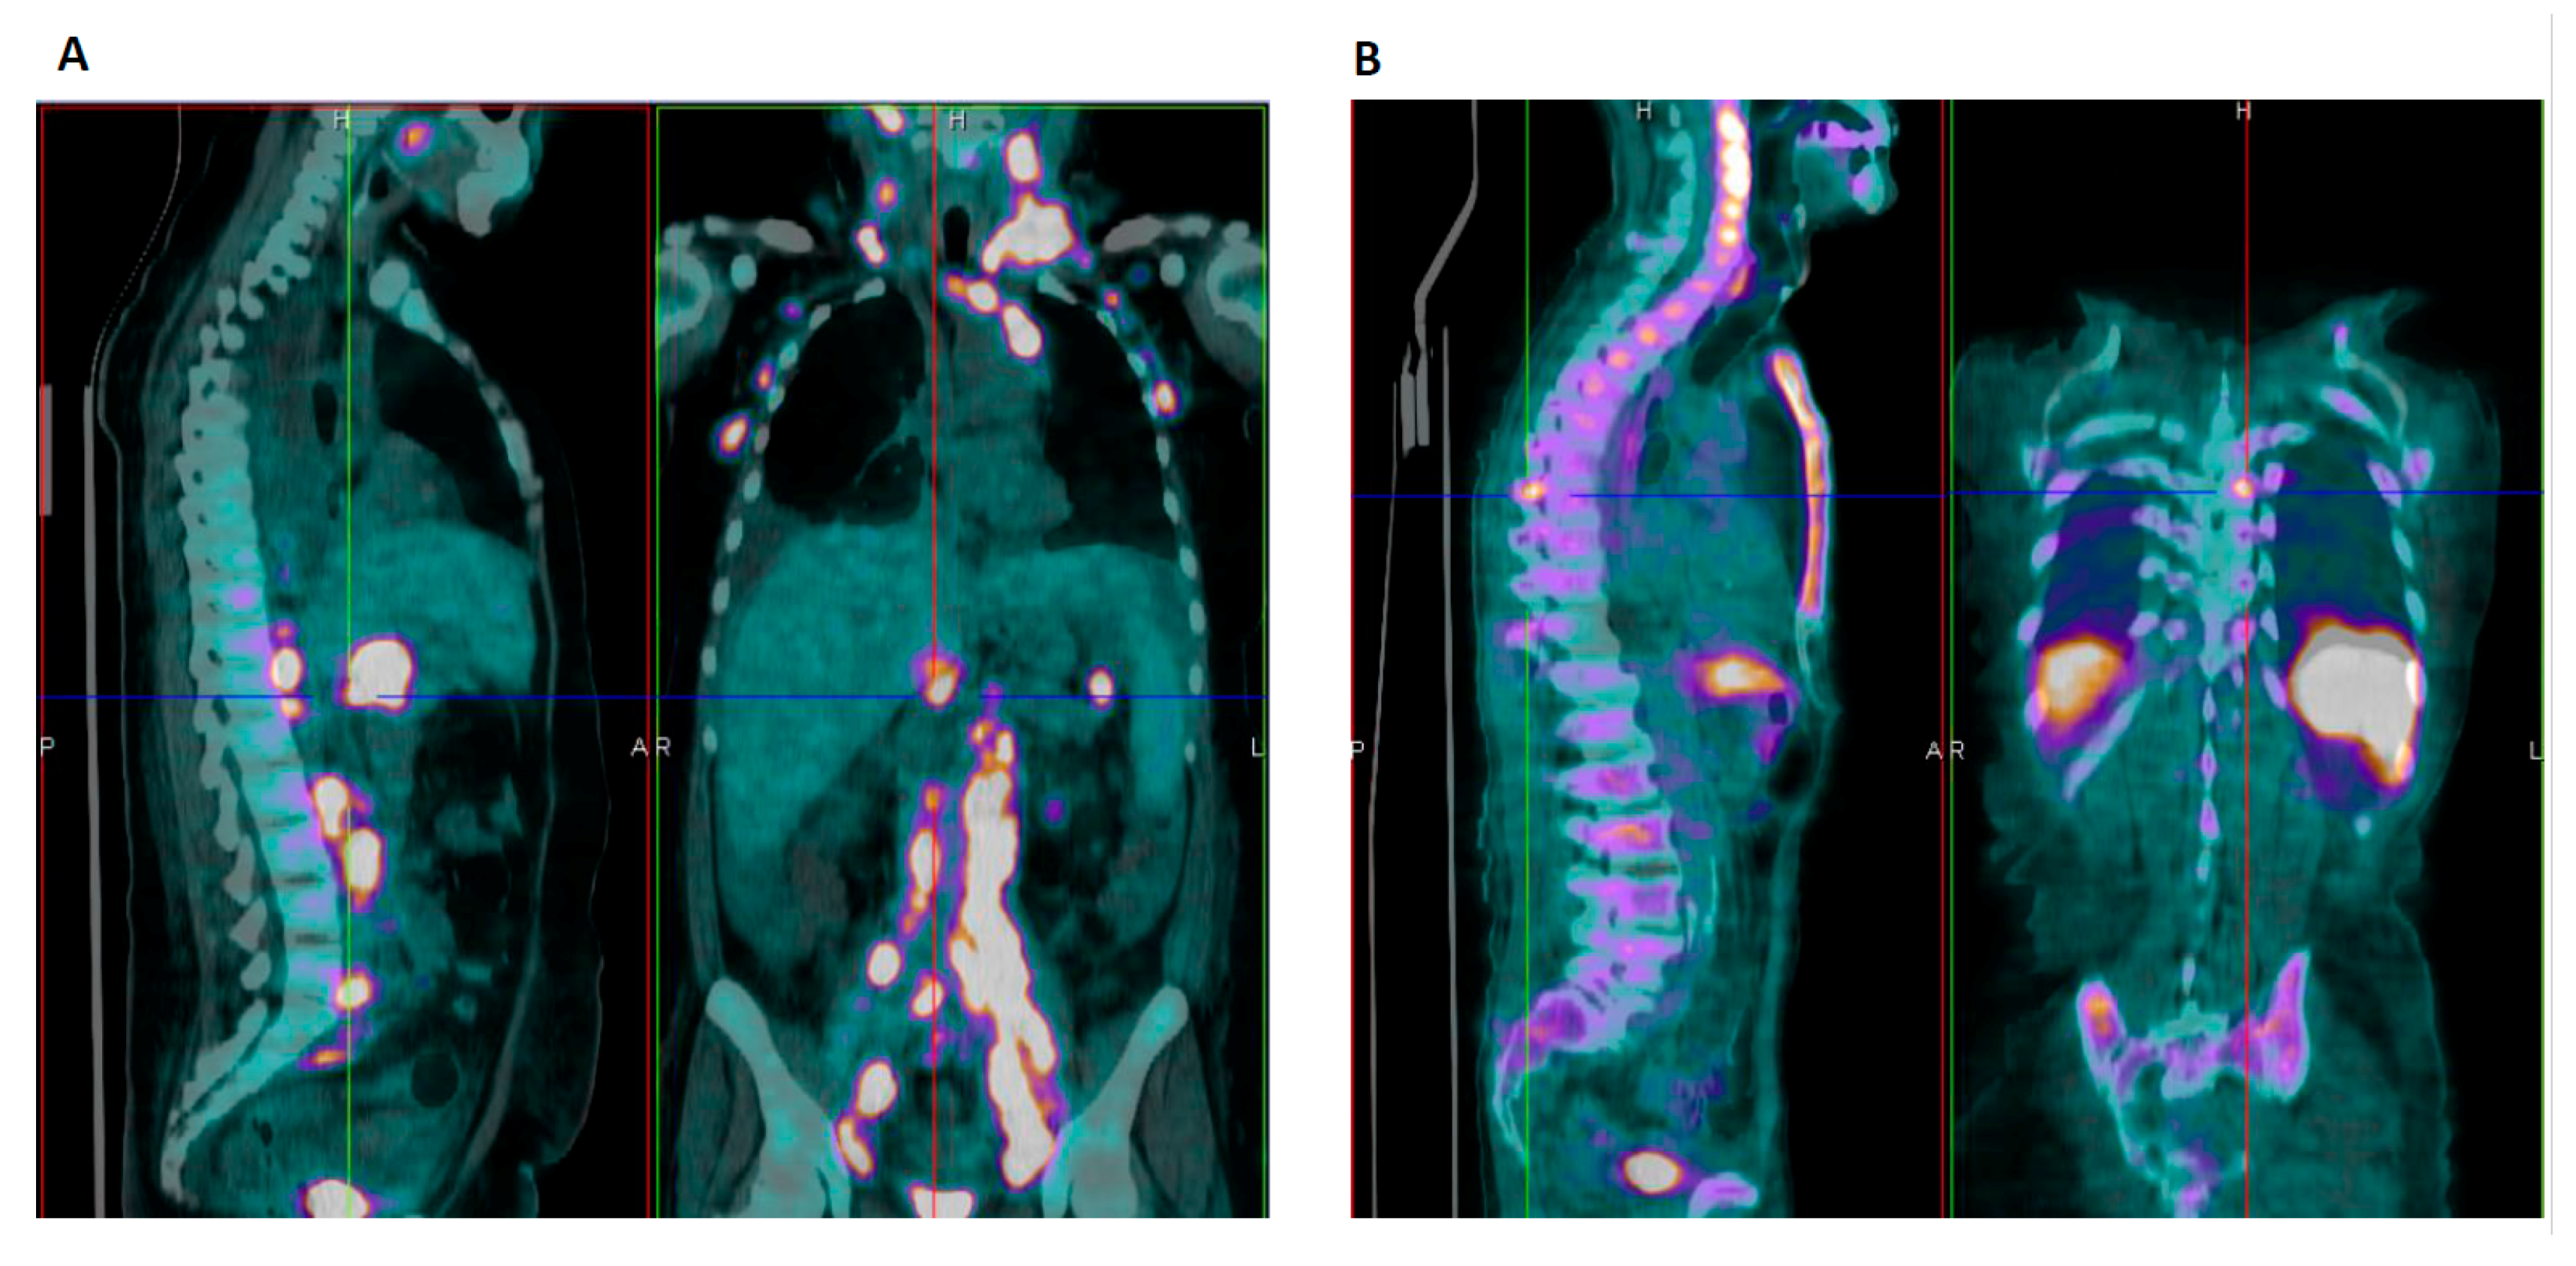

3.1. Case #1

3.2. Case #2